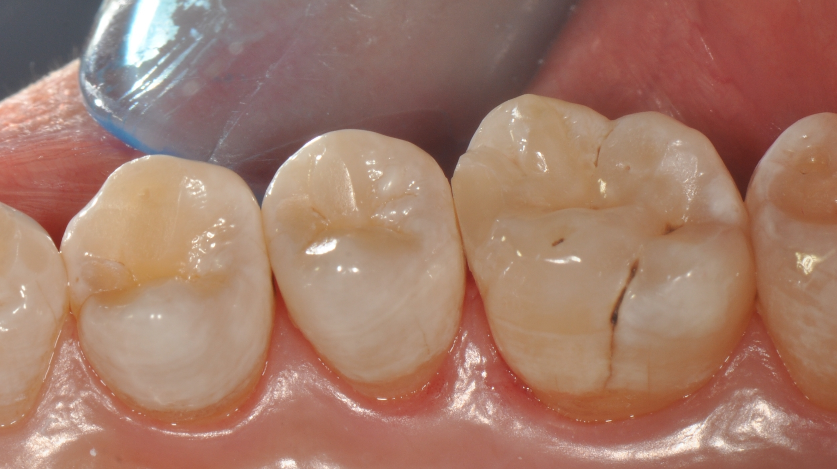

牙医-马小寒【实操病例】

右上6号牙位的近中,可见隐约龋坏